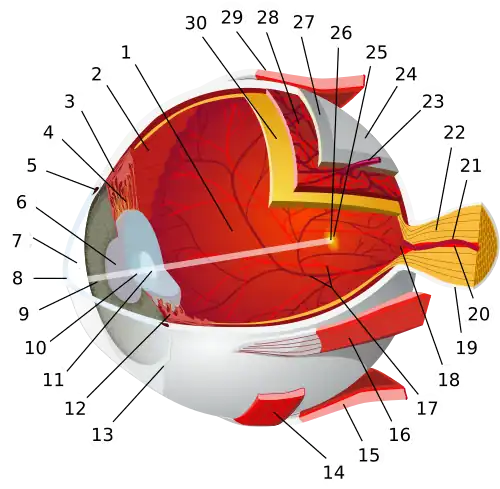

.png)